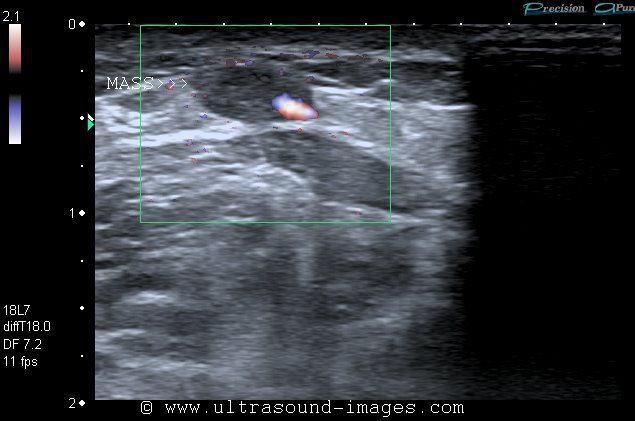

Primary venous tumor of short saphenous vein

Color Doppler image of venous mass

This middle aged male patient presented with a palpable mass of the left lower limb. Ultrasound shows a solid mass along the wall of the left short saphenous vein. Color Doppler and Power Doppler images of the mass show moderate vascularity of the mass within the superficial wall of the short saphenous vein. Primary venous tumors (masses arising from the wall of the vein) are usually malignant and relatively rare. Often they are known to metastatize easily and are often lethal. Among the primary venous malignancies the least common is hemangioendothelioma and more common is the leiomyosarcoma. Ultrasound images of venous tumor of the short saphenous vein are courtesy of Dr. Ravi Kadasne, MD, UAE.